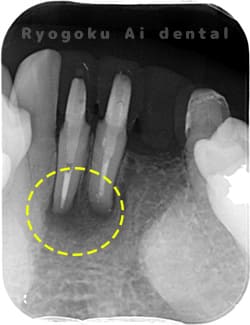

Case05

-

術後1年後レントゲン

- 原因

- 歯根嚢胞

- 治療内容

- 歯根端切除法

- 治療費用

- ¥77,000

下の前歯の違和感が取れない、響く感じも強いとのことでご来院された患者様です。歯根端切除術を行い、術後の経過も良好です。

<リスク・副作用>

外科手術のため、術後に出血、痛みや腫れ、違和感を伴います。口腔内の状態によっては適応できないことがあります。歯根端切除で治らなければ抜歯を検討しなくていけない場合もあります。